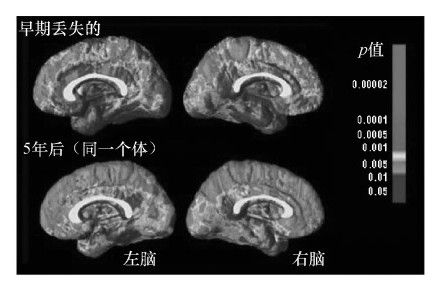

从生物学上讲,一项为期5年的研究发现,EOS儿童会比没有精神障碍的儿童丧失更多大脑灰质(Kranzler et al.,2006)。这种丧失同时出现在大脑两侧,并由前向后发展,这表明大脑功能出现了严重的生物学退化(Vidal et al.,2006)。从行为学上看,仅8%~20%的EOS患者所有症状都能获得缓解,大部分患者的症状会伴随终生(Eggers&Bunk,1997;Röpcke&Eggers,2005)。甚至与成年发病的精神分裂症患者或有其他精神病性障碍的儿童相比,EOS患者的损害也更严重。他们患病期更长,需要更长期的精神病护理,社会功能及独立生活能力损害更大(Hollis,2000;Kranzler et al.,2006)。唯一让人乐观的是,EOS的智商稳定,甚至在发病13年后仍然如此(Gochman et al.,2005)。很明显,这种病起病越早,预后越差。

所有青少年都会经历突触修剪。然而,如上面功能性磁共振成像图所示,早发性精神分裂症患者该过程的发展速度非常快。洋红色表示神经元丢失最多的区域,蓝紫色表示神经元丢失最小的区域。 在上排图中(13岁),神经元丢失最多的区域在前额叶,该区域通常与推理和问题解决有关。5年后,18岁时(下排),神经元丢失涉及的区域更广泛,涵盖了几乎所有的大脑区域。